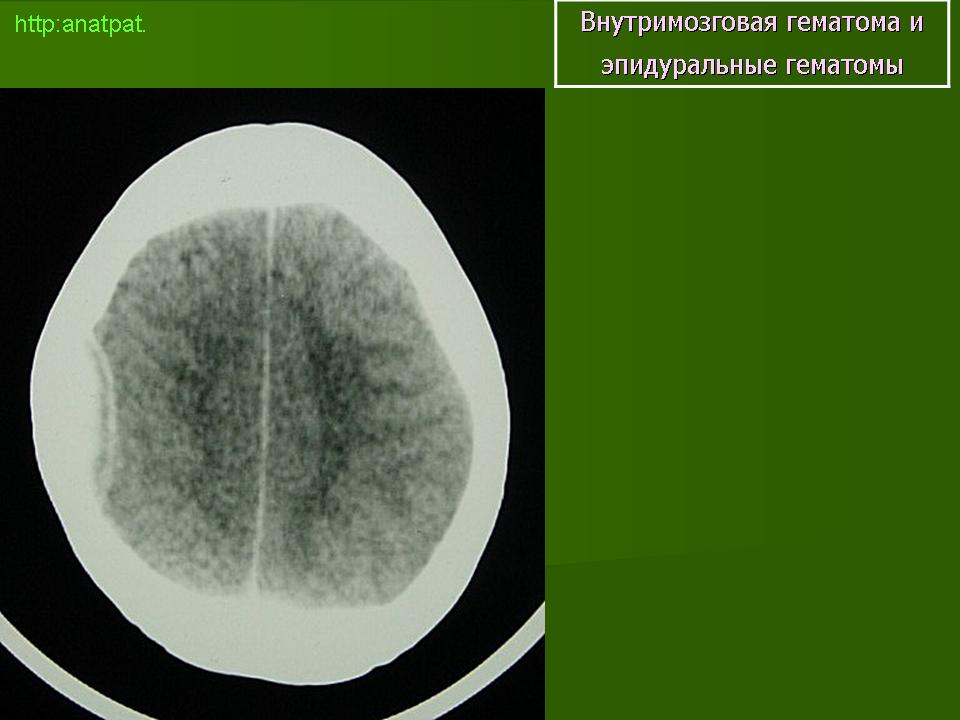

Внутримозговые гематомы